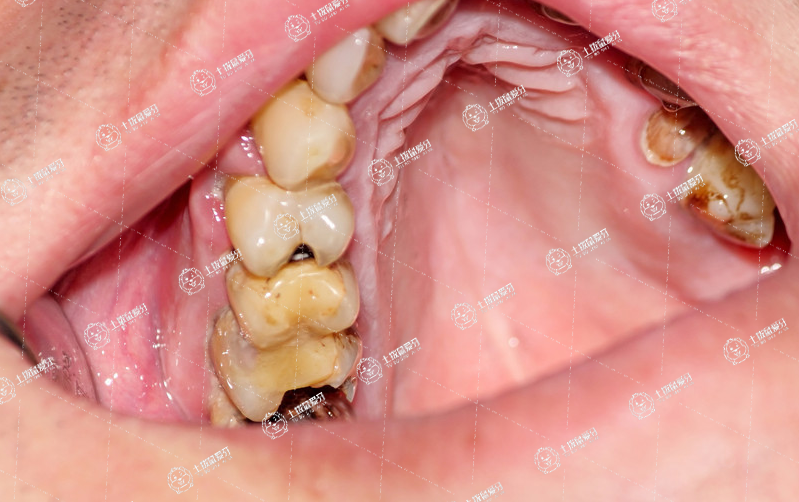

根管治療是我們牙科很常用的一一個(gè)治療措施,它是分不同的步驟進(jìn)行的。第一步,我們通常是開髓,就把牙齒斷開,緩解牙齒的炎癥和疼痛。第二步,我們要把壞死的牙神經(jīng)去除,進(jìn)行根管的消毒和預(yù)備,這個(gè)時(shí)候,我們一-方面是機(jī)械的預(yù)備,有的時(shí)候還會(huì)封一-些化學(xué)的藥物制劑來進(jìn)行殺菌和清潔。第三步稱之為根管充填,就是我們把消毒預(yù)備好的根管,用人工的牙科材料進(jìn)行嚴(yán)密的充填治療,這樣可以讓細(xì)菌沒有地方呆,達(dá)到一一個(gè)永久性的治療目的。通常第四步就是,我們最后把我們牙齒鉆開的洞和缺損的部位,用牙科材料進(jìn)行良好的恢復(fù),最后可以恢復(fù)牙齒良好的外形、功能。這是通常我們做根管治療的四個(gè)步驟,大家可以選擇性的進(jìn)行。

根管治療的步驟是開髓、拔髓、根管預(yù)備、根管充填,適用于牙神經(jīng)已經(jīng)感染了或者牙神經(jīng)預(yù)計(jì)會(huì)感染的情況。

根管治療就是牙神經(jīng),專業(yè)上叫牙髓,老百姓就叫牙神經(jīng),它感染之后就成年人因?yàn)樗难\(yùn)非常差,是從牙根最底下那根尖小孔里面進(jìn)去的,它的血運(yùn)非常差,是屬于末梢的循環(huán),一旦感染之后,發(fā)炎之后,它沒有再恢復(fù)的可能性,所以這種情況下只能把牙神經(jīng)摘除。

牙神經(jīng)摘除完了之后,并不是說就能夠保證它沒問題了,因?yàn)樗锩嬉粋€(gè)空腔,還有細(xì)菌可能就容易進(jìn)去感染,再造成下一次的感染,所以這種情況下不只是要給它摘除,完了之后還把里面給它填滿,讓細(xì)菌不能再進(jìn)去。

1、先要把牙齒鉆開,叫開髓。

2、把里面牙神經(jīng)拔出來,叫拔髓,然后拔干凈之后,還要把根管做的比較通暢,根管壁上殘留的一些感染的東西給去掉,這一部分叫根管預(yù)備。預(yù)備好了之后,然后再給它填進(jìn)去根充的材料,把里面填滿填實(shí),就這樣細(xì)菌就進(jìn)不去了。